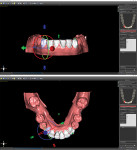

Based on the fact that the literature on surgically assisted orthodontics commonly reports that it is safe, effective, has a low incidence of relapse, and results in shorter treatment times, the decision was made to develop an accurate workup using available digital technology that has not yet been utilized in this manner. Given the close proximity of the roots of the lower incisors (Figure 2), performing this type of corticotomy freehand could lead to irreversible issues and possibly permanently damage the patient's natural teeth. In addition, limited funding prevented the use of advanced surgical grafting required for periodontally accelerated osteogenic orthodontics or the use of the corporate entity Invisalign.

A cone-beam computed tomography (CBCT) scan (PreXion 3D, PreXion, Inc.) of the upper and lower jaws was obtained. This DICOM file was then imported into the treatement planning software (Blue Sky Plan®, BlueSkyBio) as a new project. Next, a vinyl polysiloxane impression was taken of the patients' full lower arch, and a stone model was poured. This model was scanned, and the impression DICOM data was then imported into the planning software and meshed together with the DICOM data of the lower jaw.

The fabrication of the corticotomy guide was completed by first creating a "generic guide" on the digital model in the planning software. The surgical guide function is typically used for the creation of implant drill guides, but in this case, because no guide tubes were incorporated, the design was just a basic, 3-mm uniform thickness shell that sat over the arch (Figure 3). This provided the foundation for the corticotomy guide. A free 3D modeling application (Meshmixer, Autodesk, Inc.) was then used to create a 15 mm x 15 mm plane measuring 1-mm thick to correspond to the 1-mm width of the piezoelectric surgery tip (Figure 4). After this shape was saved and imported into the planning software, it was duplicated several times and precisely positioned in the surgical guide between the roots of the individual teeth where the corticotomies were to be performed (Figure 5). Because the planes represented the positions where the piezoelectric surgical bone cuts would be made, the plane shapes were checked in all views to ensure that no portion impinged into the tooth roots (Figure 6). Next, the data for the surgical guide and each of the planes were exported and reopened within the 3D modeling application to facilitate a Boolean subtraction. In this manner, the planes were subtracted from the data for the guide, leaving 1-mm slots where the piezo tip could be inserted (Figure 7). Once all of the planes were subtracted, the data was imported back into the planning software to verify the accuracy (Figure 8), and the guide was printed (Objet30 3D printer, Stratasys) (Figure 9).